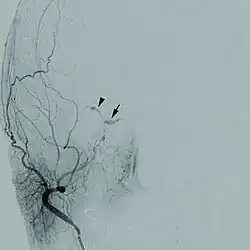

Cerebral angiogram of a carotid-cavernous fistula | |